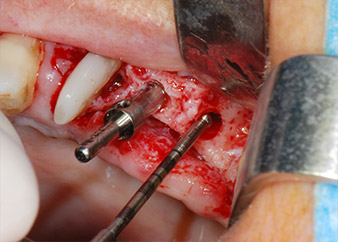

Implant beds were prepared at sites 25 and 26 with rotary instruments, used in a contra-angle handpiece with a 20 : 1 transmission ratio with an updated powerful implant motor (Implantmed, W&H) (Fig. 8).

The final preparation next to the sinus was again carried out with a piezoelectric instrument (Piezomed, insert S2).

The implants (Restore, Keystone Dental, diameter 3,75 mm, length 8.0 mm) were placed with the implant motor

(Figs. 11 and 12).

Low speed insertion of implant 26

Fig. 11: Low speed insertion of implant 26 with a torque limitation of 35 Ncm.